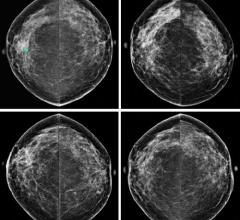

Despite decades of progress in breast imaging, one challenge continues to test even the most skilled radiologists ...